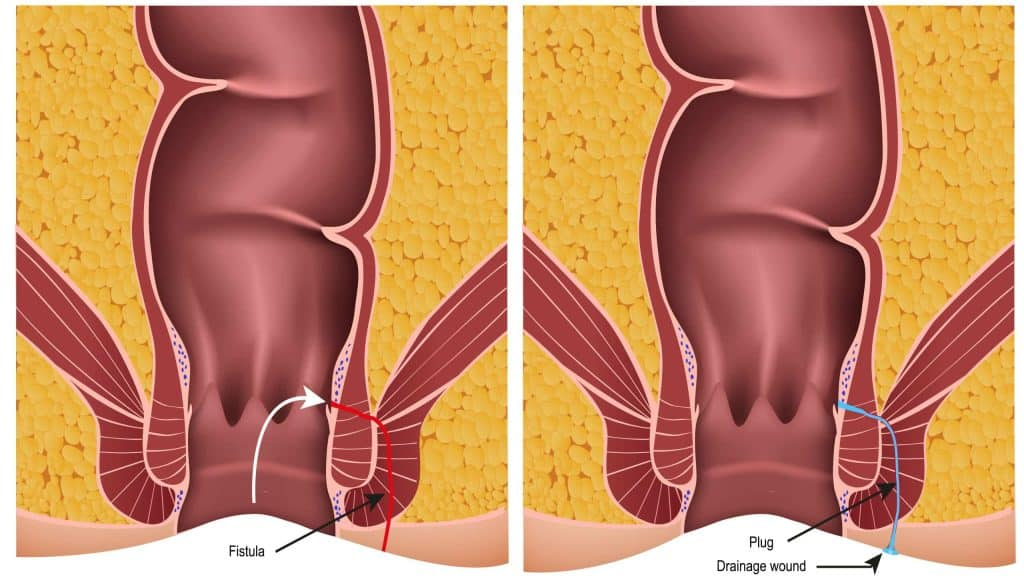

VAAFT (Video-Assisted Anal Fistula Treatment) is a modern, minimally invasive technique used to treat anal fistulas ...

What is VAAFT and How Does It Treat Fistula-in-Ano?

Many patients come to us with a common question: “Doctor, can Anal Fistula …”